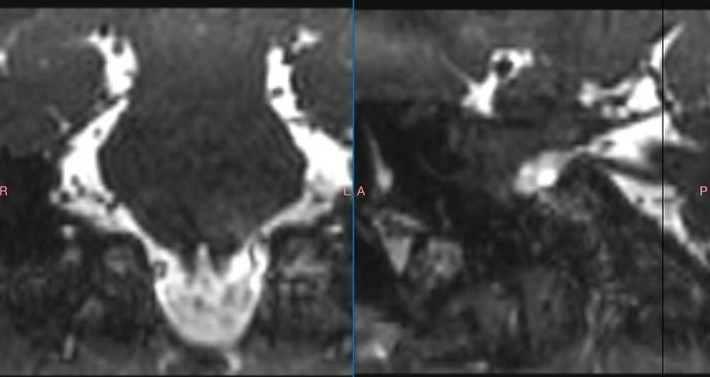

Пациентке сделали над небольшой разрез за ухом и просверлили отверстие размером меньше двух сантиметров, благодаря чему врач смог добраться к структурам мостомозжечкового угла под микроскопом. Хирург смог разъединить спайки, уложить специальный инертный материал и устранить компрессию. Любовь выписали через неделю после операции. Чтобы понять, насколько операция была эффективной, нужно время, но пациентке уже стало лучше.

Оказалось, что Юрий Кивелёв в 2007 году прослушал лекцию американского нейрохирурга Питера Джаннетты в городе Питсбурге (США). Тогда путь врача составил тоже около 10 тысяч километров. Американский специалист — основоположник микроваскулярной декомпрессии, а также разработчик техники операции по лечению невралгии тройничного нерва.

Сейчас именно микроваскулярная декомпрессия является золотым стандартом лечения невралгии тройничного нерва. Спустя почти 20 лет знания, полученные на лекции, пригодились карельскому врачу в работе, рассказал министр здравоохранения Карелии Михаил Охлопков.